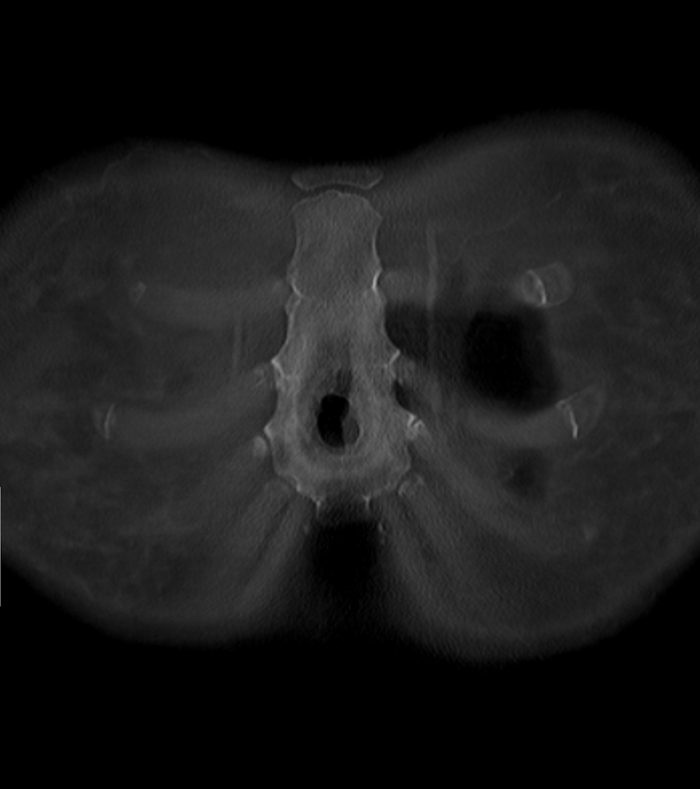

Пациентка, 64 года, перенесла двустороннюю мастэктомию (удаление обеих молочных желёз) по поводу рака 14 лет назад с пластикой с обеих сторон двухкамерные имплантами. Сейчас клинически подозревают фиброз капсулы и возможно разрыв левого импланта. Для подтверждения диагноза провели МРТ молочных желёз (только нативную часть протокола, т.е. без в/в введения контрастного вещества, от которого пациентка отказалась).

Начнём с краткого обзора здорового импланта:

Т2-взвешенное изображение

где центрально расположена камера, заполненная физ.раствором (голубой цвет), на периферии - камера, заполненная силиконом (красный цвет), и отграничено это всё фиброзной капсулой, которой тело старается отграничить инородный объект (пунктирная линия):

если мы сравним правый имплант с левым, то разница очевидна, тут не надо быть рентгенологом, чтобы понять что что-то тут не то, а именно сам имплант меньше, интенсивность сигнала иная (цвет более тёмный) + видны какие-то линии внутри импланта (красные стрелочки):

Линии эти - так называемый признак "лингвини" (или по-английски linguine sign), т.к. похожи они на одноимённую итальянскую пасту лингвини:

и являются ни чем иным как спавшимися стенками камер имплантов, что указывает на внутрикапсульный (в пределах образовашейся фиброзной капсулы) разрыв импланта, но без свободного выхода содержимого в окружающие мягкие ткани.

Интенсивность сигнала поменялась из-за того, что физ.раствор частично смешался с силиконом, и вследствие этого определяются пузырьки физ.раствора в силиконе - т.н. признак "салатного масла" или "salad oil sign" (капли, как при добавлении масла в воду):

которые я отметил красными стрелочками:

и на секвенции с подавлением воды, которая становится на картинке "чёрной" (синяя звёздочка), а силикон остаётся "белым" (красная звёздочка):

Имплант, соответственно, больше не жизнеспособен и его следует заменить.